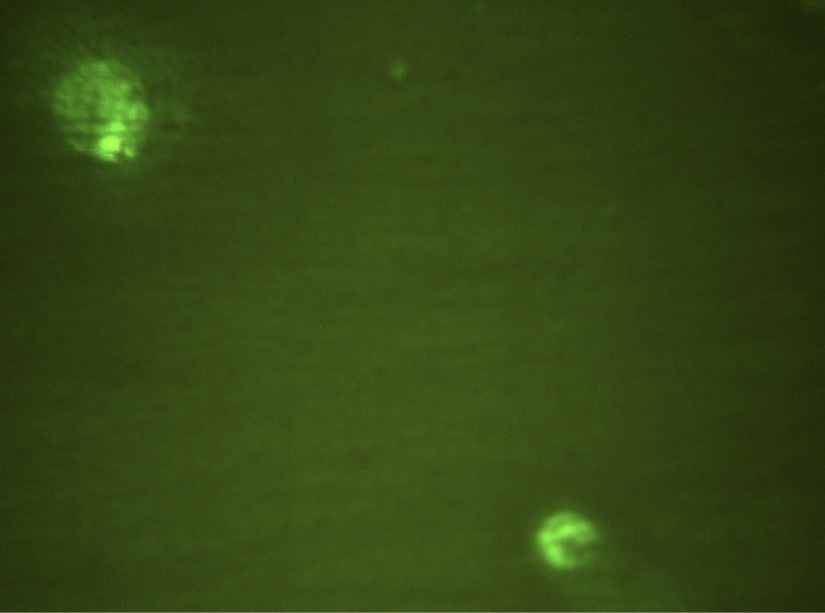

На рис. 1 в поле зрения люминесцентного микроскопа зафиксированы 2 клетки, экспрессирующие CD282 (TLR2), меченные FITC. Видны ярко окрашенные скопления в виде гранул. На рис. 2 в фазовом контрасте видны 4 клетки, выделенные из экссудата пародонтального кармана. На рис. 3 при люминисцентном микроскопировании представлены эти же 4 клетки с неярким диффузным окрашиванием CD284-FITC (TLR4). Таким образом, в результате данного пилотного исследования выявлена и визуализирована экспрессия рецепторов врождённого иммунитета TLR2 и TLR4 в десневой жидкости и экссудате пародонтального кармана при ХП.

Рис. 1. Клетки десневой жидкости, экспрессирующие CD282. Окраска FITC, ×1000.

Рис. 3. Клетки десневой жидкости, экспрессирующие CD284. Окраска FITC, ×1000.